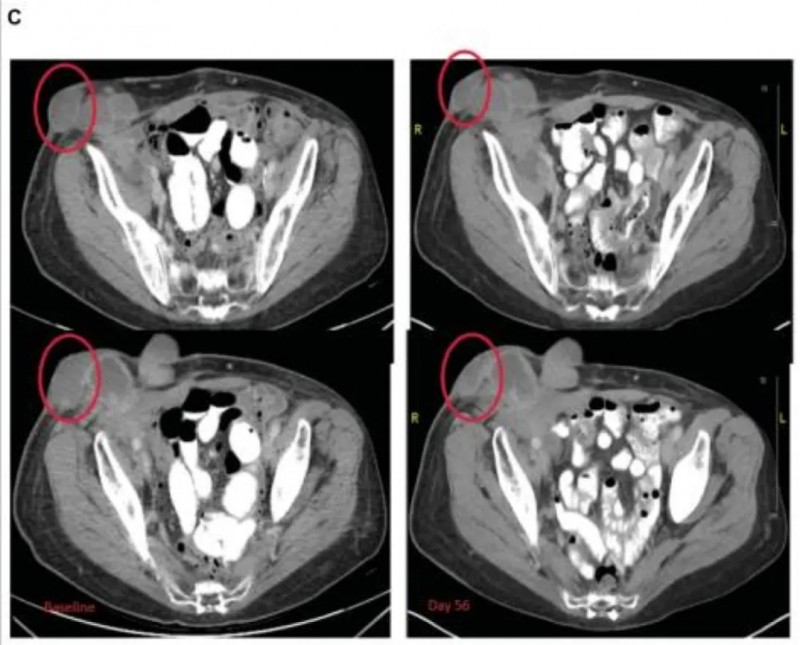

结果显示:疫苗治疗后的效果呈现出持续改善的趋势,治疗前的CT复查显示,患者左下叶病变已缩小至3cm×3cm(详见下图A),左上叶病变直径<1cm,同时存在放射治疗引发的包裹性胸腔积液;疫苗治疗3个月后,左下叶肿瘤进一步缩小至2cm×2.1cm(详见下图B);治疗6个月后,肿瘤体积降至1.5cm×2.3cm(详见下图C),较初始放化疗后的大小缩小30%,且后续趋于稳定,同期患者的胸腔积液减少、局部淋巴结缩小。

▲图源“Hum VaccImmunother”,版权归原作者所有,如无意中侵犯了知识产权,请联系我们删除